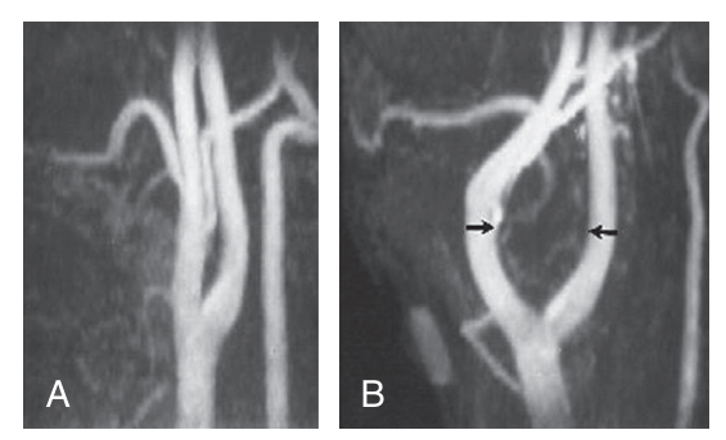

Arteriography-Shows the carotid bifurcation to be splayed open by the mass which is rich in vascularity

What is Lyre sign in CT scan?

angiogram - most likely carotid body tumour

Six genes have been associated with the development of paragan- glioma, including RET, VHL and NF1. Paragangliomas may also be hereditary, included as part of genetic syndromes such as von Hip- pel–Lindau, neurofibromatosis type I, MEN 2A and MEN 2B. Spo- radic cases may be caused by germline mutations. The three most common paragangliomas in the head and neck region are carotid body tumour, glomus jugulare and glomus intravagale. The carotid body is located in the adventitia of the posteromedial aspect of the carotid bifurcation. Its chemoreceptors regulate ventilation in response to changes in arterial blood gases and pH. 26.18